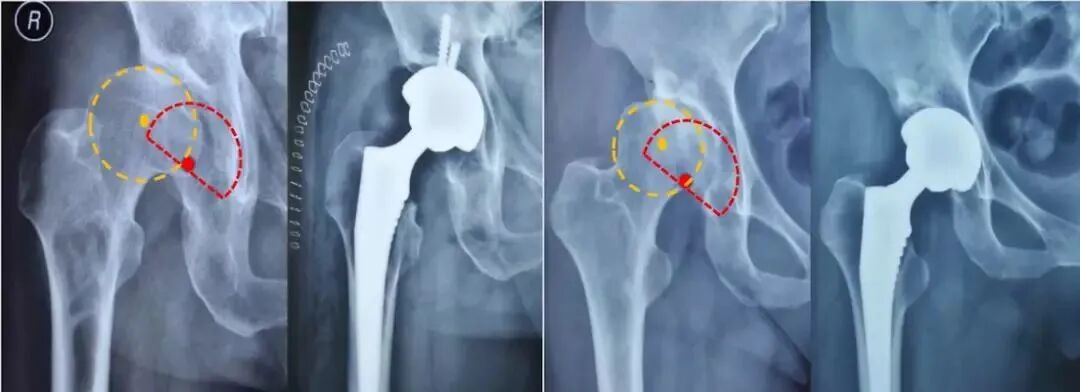

股骨假体评估:

①柄-髓腔轴线夹角;

②通过正位X线片上测量假体柄长轴与股骨长轴间夹角来确定,夹角≤3°为中心固定;

③超出3°为内翻或外翻固定;

——远端尖端在外侧-内翻

——远端尖端在内侧-外翻

前倾角:10°-15°;

必须由侧位片评估。

注意:部分假体自带前倾角(绝大多数不带),术中应予注意,以免术中再前倾放置引起前倾过度。